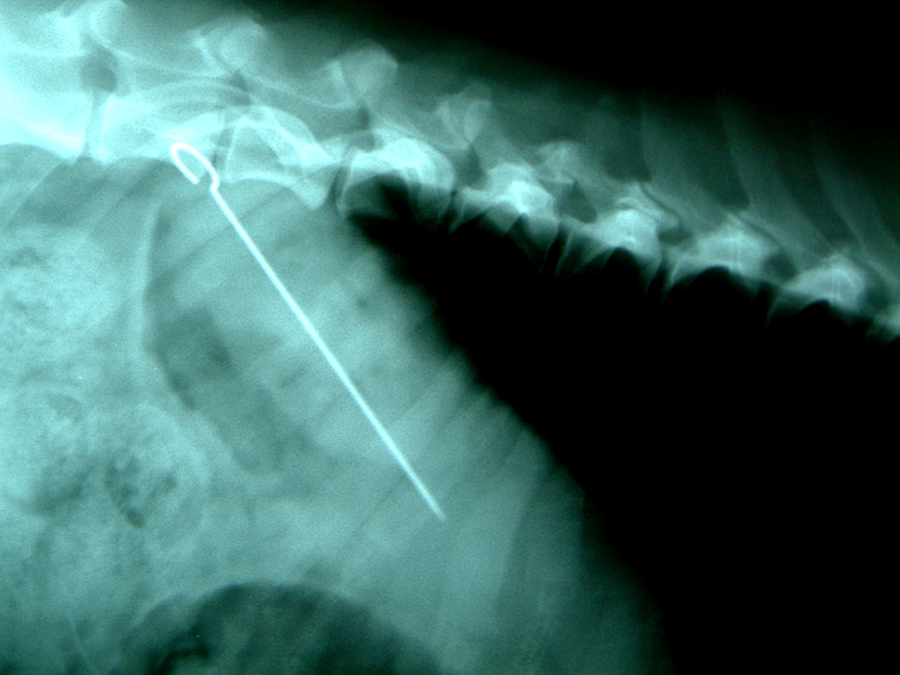

Gesamtes Spektrum der Weichteil- und Knochenchirurgie